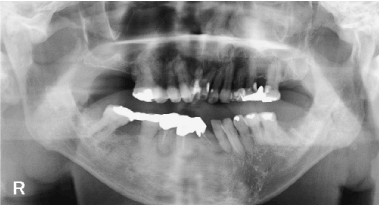

The panoramic X-ray at the patient's first visit to our hospital is presented in Figure 1. The bone mineral density of the alveolar portion was high over the entire jaw. The left upper jaw 8 and the left lower jaw 7 and 8 showed caries and tooth extraction due to poor cleaning performance. The risk of periodontal disease infection was large. A chest X-ray taken with the patient under general anesthesia at the screening in April 2018 is shown in Figure 2. Cardiac hypertrophy was recognized due to insufficient mitral regurgitation.

Figure 1. Panoramic X-ray